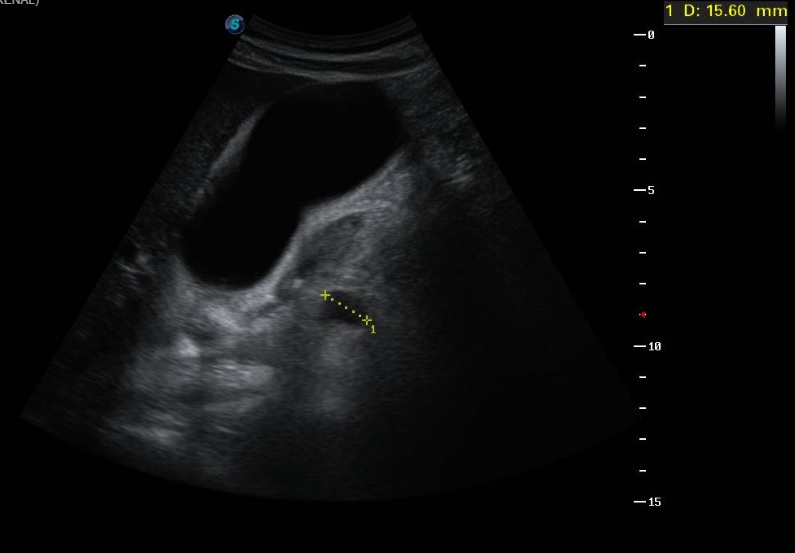

Ecografía clínica a pie de cama: Parénquima hepático y esplénico de ecoestructura preservada. Vesícula biliar marcadamente distendida con imagen hiperecogénica de 2 cm en porción declive compatible con litiasis. Dilatación de la vía biliar intrahepática difusa así como dilatación del colédoco.

La litiasis y la dilatación de la vesícula biliar encontrada en la ecografía clínica no justificaba todo el cuadro, por lo que solicitamos ecografía reglada al equipo de radiología. En ella informan marcada dilatación de la vía biliar intrahepática, con un colédoco de hasta 15 mm, y estructura mamelonada de aproximadamente 7 cm en cabeza pancreática. Se completa estudio con Tomografía Axial Computarizada que confirma masa en cabeza pancreática compatible con adenocarcinoma que condiciona dilatación de la vía biliar retrógrada.